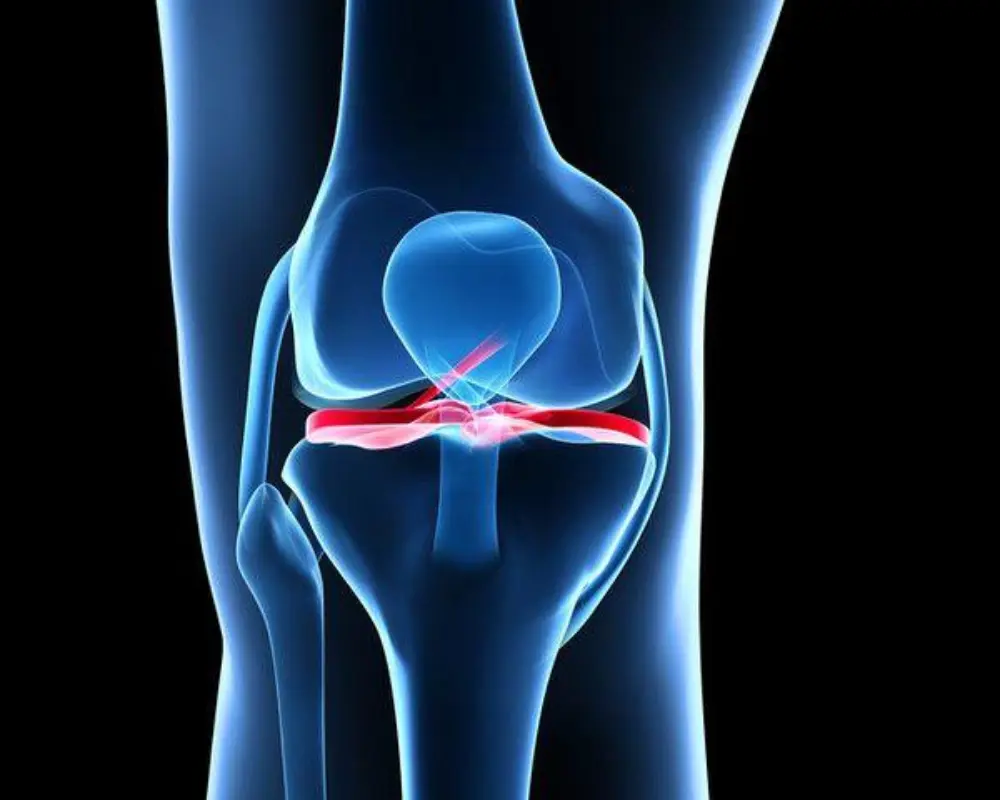

Ligament Injuries

A Musculoskeletal MRI Scan helps detect ligament tears such as ACL injuries and tendon damage in joints like the knee, shoulder, or ankle. It shows the extent of injury clearly and supports the right treatment planning.